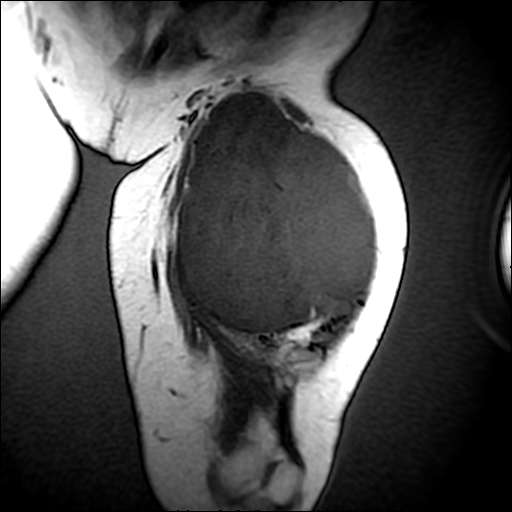

左侧大腿外伤10余年,当时情况不清,发现左侧大腿肿胀7年余,而后又有多次外伤史,近1年来出现疼痛,减重半年。查体:左侧大腿肿胀明显,皮温、肤色正常。

增强

软组织肿块,股骨破坏,增强不均匀强化-----支持恶性肿瘤